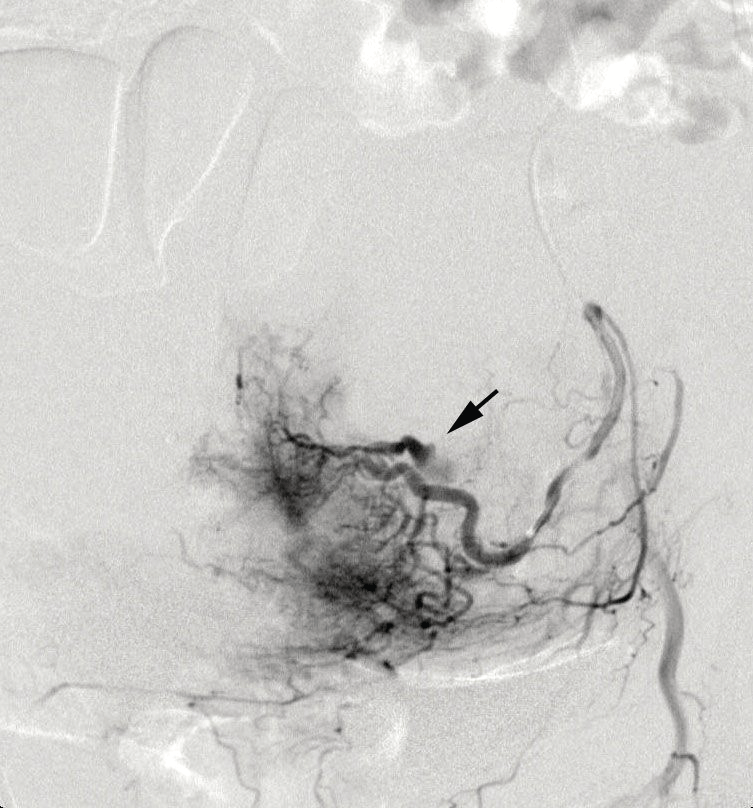

Angiographic control performed during procedure showed an important active bleeding from the pseudoaneurysm and so cyanoacrylate 1 ml was injected before metallic spirals to achieve complete embolization (Figure 1,2).

Figure 1: Angiogrphic finding of bleeding left UAP

View Figure 1